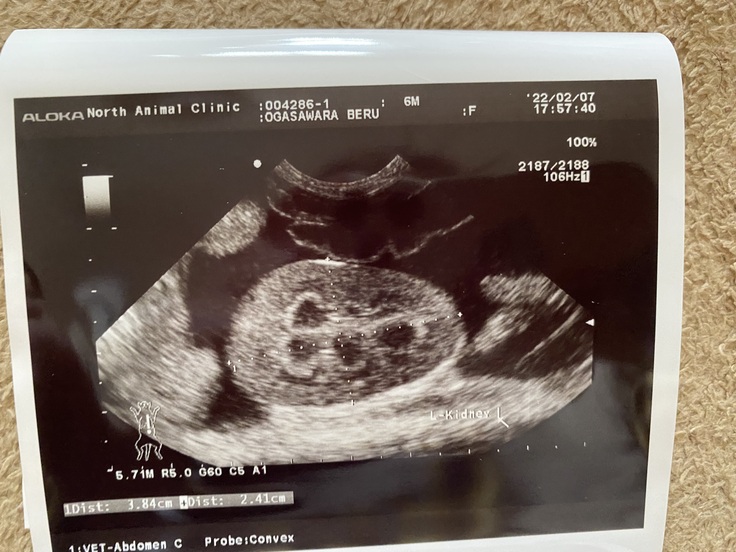

B病院での血液検査項目が少ないとのことで、改めて

・血液検査

・エコー検査

・腹水検査をしました。

そして残念ながらこの病院でも

「FIPの可能性が高い」

と言われてしまいました。

また、これまでは腹水が溜まっているから

ウェットタイプと言われていましたが、

エコー検査の結果から混合タイプ

かもしれないとも言われました。